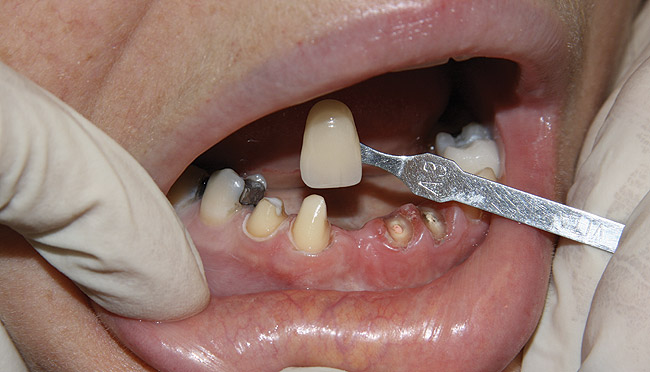

Figure 11  Original feldspathic porcelain crown placed by restorative dentist, tooth No. 9—facial view.

Figure 11

Figure 12  Localized moderate gingival inflammation on facial aspect of No. 9 (2 years post-cementation).

Figure 12

Two years later, however, the patient returned to her restorative dentist’s office complaining that “something felt different” on tooth No. 9. Localized moderate gingival inflammation was present on the facial aspect of No. 9 (Figure 12). A straight facial probing depth of 6 mm and severe bleeding on probing were also evident facially, suggesting a vertical root fracture.